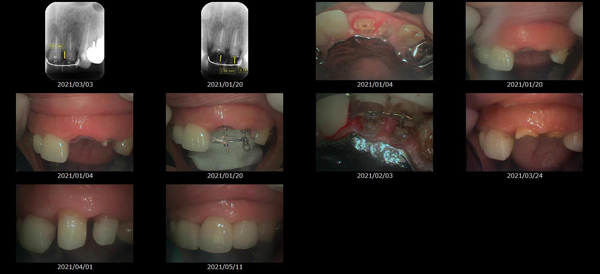

救歯MTM

虫歯が大きくて残せない歯、転倒などの事故により歯が根の深いとこで折れてしまったなどで、抜かざるを得ない歯を、骨の中に埋まっている健全な根を、骨の上に矯正的に引き上げることで、その歯を抜かず温存、救歯できる可能性のある治療方法です。

この特別な診療である救歯MTMは、以下のような特徴があります。

①健全な歯を、歯肉から見える位置にまで引き上げることで

根の治療の成功率を上げることが出来る。唾液には沢山の細菌がいます。唾液が入らない環境での根の治療を(神経の治療)を行うことで神経の治療、根の治療の成功率は格段と上がります。

②骨の上にある歯と土台で支える被せもの製作できる。

被せものを土台だけに頼ることなく、引き上げた健全な歯でも支えることで、歯への被せ物がしっかりと装着できるようになる。

③抜かずに歯を活かすことで、隣の歯を削るブリッジやインプラントにしないで済むことがある。

歯を矯正的に引き上げることで、その歯を救歯できるだけでなく、隣の歯を削るなどの侵襲を回避できる場合がある。

救歯治療と審美性の両立

当院では様々な治療の基礎に審美と機能の両立というテーマがあります。

- > 歯を矯正的に引き上げることで、骨の中の根の長さは短くなりますが、その短さでも安定するという診断をした場合のみ施術になります。 残せる歯、根の長さが短い場合は、この救歯MTMの治療対象とならない場合がございます。

- > 治療期間が数か月~1年に及ぶ場合がある。

- > 費用が自費診療 44,000円 ~ 66,000円

- > 救歯MTMは救歯BTAセラミックと併用治療が必要な場合があります。

症例